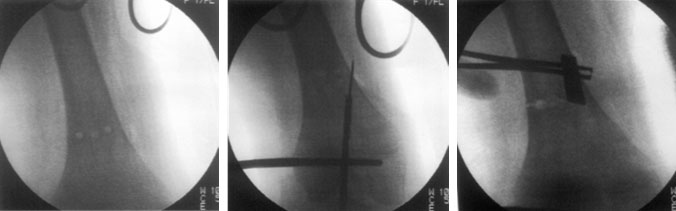

Percutaneous osteotomy is performed using minimally invasive technique through a small incision, just enough to permit the osteotome with minimal soft tissue stripping.

The pictures here show the xrays done during surgery. Drill holes are made using the jig. The entry path for the nail in the distal part of the bone is marked using k-wire and cannulated drill bit. Another instrument like osteotome is used to mark the correct angle.

The holes are then connected and osteotomy is completed using the osteotome.